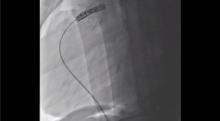

The second case involved a 15-year-old patient with the same clinical presentation as the first case. The intra-operative RVOT angiogram showed a maximal diameter of 33 mm, precluding the insertion of a trans-cutaneous Melody pulmonary valve. After a partial upper sternotomy, the RVOT was plicated, creating a tubular structure with a maximal diameter of 23 mm. The plicated RVOT acted in this way as the landing zone for a 22 mm trans-cutaneous Melody pulmonary valve implantation. The post-operative angiogram and echocardiogram showed perfectly functional pulmonary valve prosthesis with no stenosis or regurgitation.